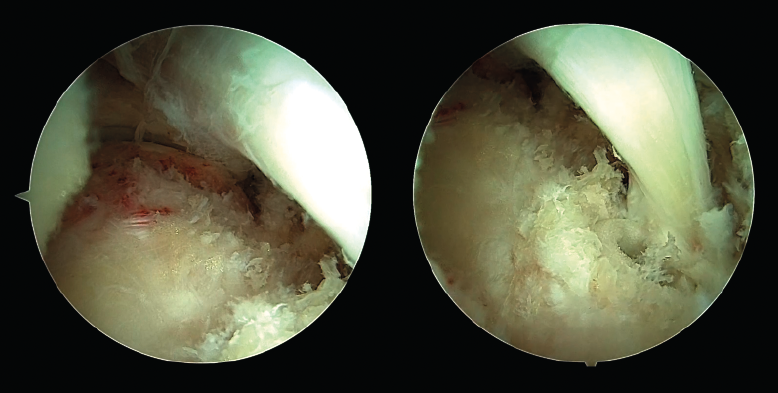

El diámetro adecuado del túnel depende del diámetro del tendón FHL, que se mide una vez externalizado y tras ser seccionado. La longitud del túnel debe ser al menos de 10 a 15 mm más larga que la longitud ideal del tendón FHL. Usualmente, un túnel mínimo de 30 mm de longitud debería ser suficiente, pero debe considerarse la longitud de tendón exterior al túnel (Figura 5). Una vez realizado el túnel y aún con la aguja guía transfixiando el calcáneo, se introducen las suturas en el ojal de la aguja de Kirschner. Al empujar la aguja de Kirschner desde su salida en la zona plantar, las suturas pasan a través del túnel hasta la región plantar. A continuación, al traccionar de las suturas, el tendón se introducirá en el túnel (Figura 6).

Figura 6. Tras realizar el túnel calcáneo, se carga la aguja de Kirschner con las suturas de Krackow realizadas sobre el tendón. A continuación, la aguja de Kirschner es traccionada desde su salida en la zona plantar, de modo que el tendón del músculo flexor hallucis longus (FHL) se introduce en el túnel calcáneo.

Una vez el tendón está dentro del túnel, debe ser bloqueado con un tornillo interferencial o de biotenodesis. Idealmente, el tornillo debe ser del mismo diámetro que el túnel calcáneo realizado. El tornillo se introduce guiado con un nitinol para que tome una dirección correcta. Con el tobillo en flexión plantar y traccionando de las suturas para tensar el tendón FHL, se introduce el tornillo bajo control endoscópico directo (Figura 7).

Figura 7. Visión final de la transferencia del tendón flexor hallucis longus (FHL). Izquierda: visión proximal; derecha: visión distal con visualización del tendón del FHL correctamente fijado al calcáneo con un tornillo interferencial.